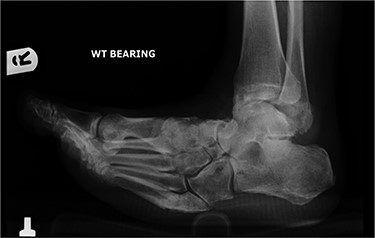

In May 2015, he had a complex midfoot reconstruction, but his foot continued to drift into varus. This was complicated by an infected ulcer on the lateral aspect of midfoot (Fig. 3). Wound infection progressed to osteomyelitis, and in May 2018, he had a hindfoot reconstruction with fusion of tibiotalar and subtalar joints using a Cerament-V-coated hindfoot nail (Figs 4 and 5).

Anterior–posterior radiograph of right ankle demonstrating tibiotalocalcaneal fusion using a hindfoot nail and screws.

Lateral radiograph of right ankle demonstrating tibiotalocalcaneal fusion using a hindfoot nail and screws.